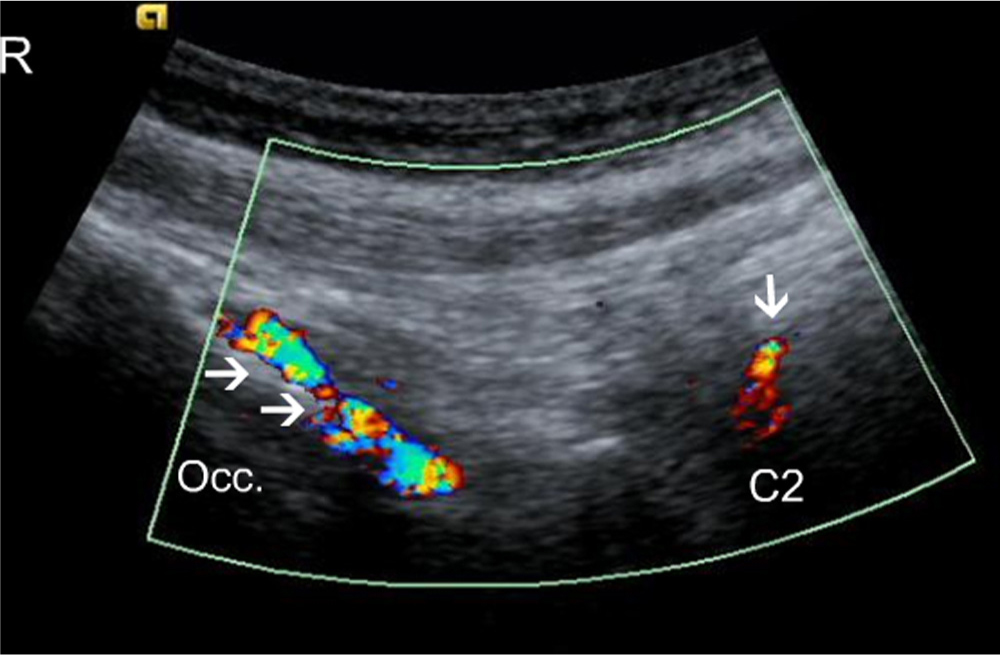

It was not possible to visualize the origin of the blood vessels exactly; however, in the suboccipital region, the high blood flow corresponded to the insertion of the semispinalis capitis and the rectus capitis posterior minor muscles. At the C1 level the high blood flow was more pronounced at the posterior tubercle, corresponding to the insertion of the rectus capitis posterior minor muscles (Figs. 1, Fig. 2, Fig. 3, 4). At the C2 level the high blood flow was found in the region of the spinous process, corresponding to the origin of the rectus capitis posterior major and the obliquus capitis inferior muscles, and bilaterally juxtapositioned to the facet joints (Figs. 5, Fig. 6, 7).

Longitudinal colour, Doppler scan of a patient. Arrows identify blood vessels jusxtapositioned to the occipital bone (Occ.); the single arrow indicates the C2 spinous process and blood flow in the vessels juxtapositioned to it. Occ., Occipital bone; R, rostral.